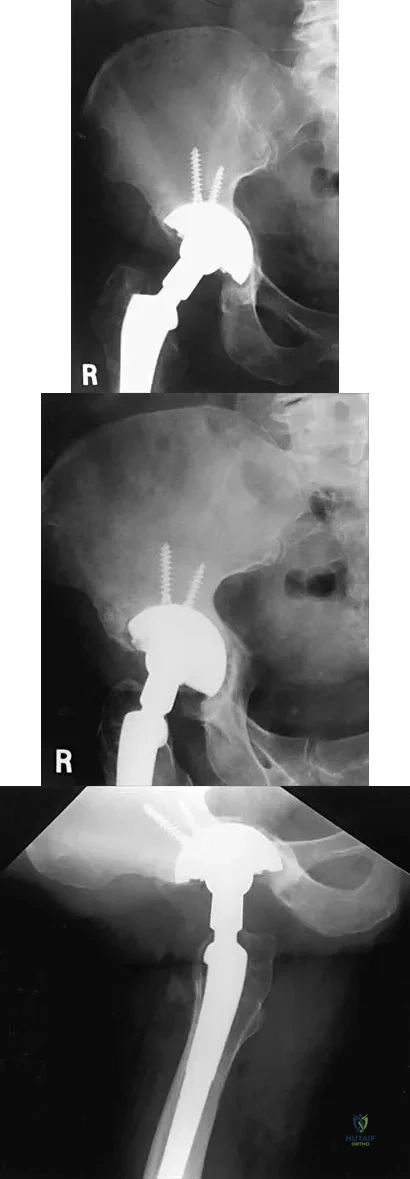

Question 33

Figures 21a through 21c show the radiographs of a 70-year-old woman who has persistent pain with activity after undergoing hip revision 6 months ago. Treatment should now consist of

Explanation